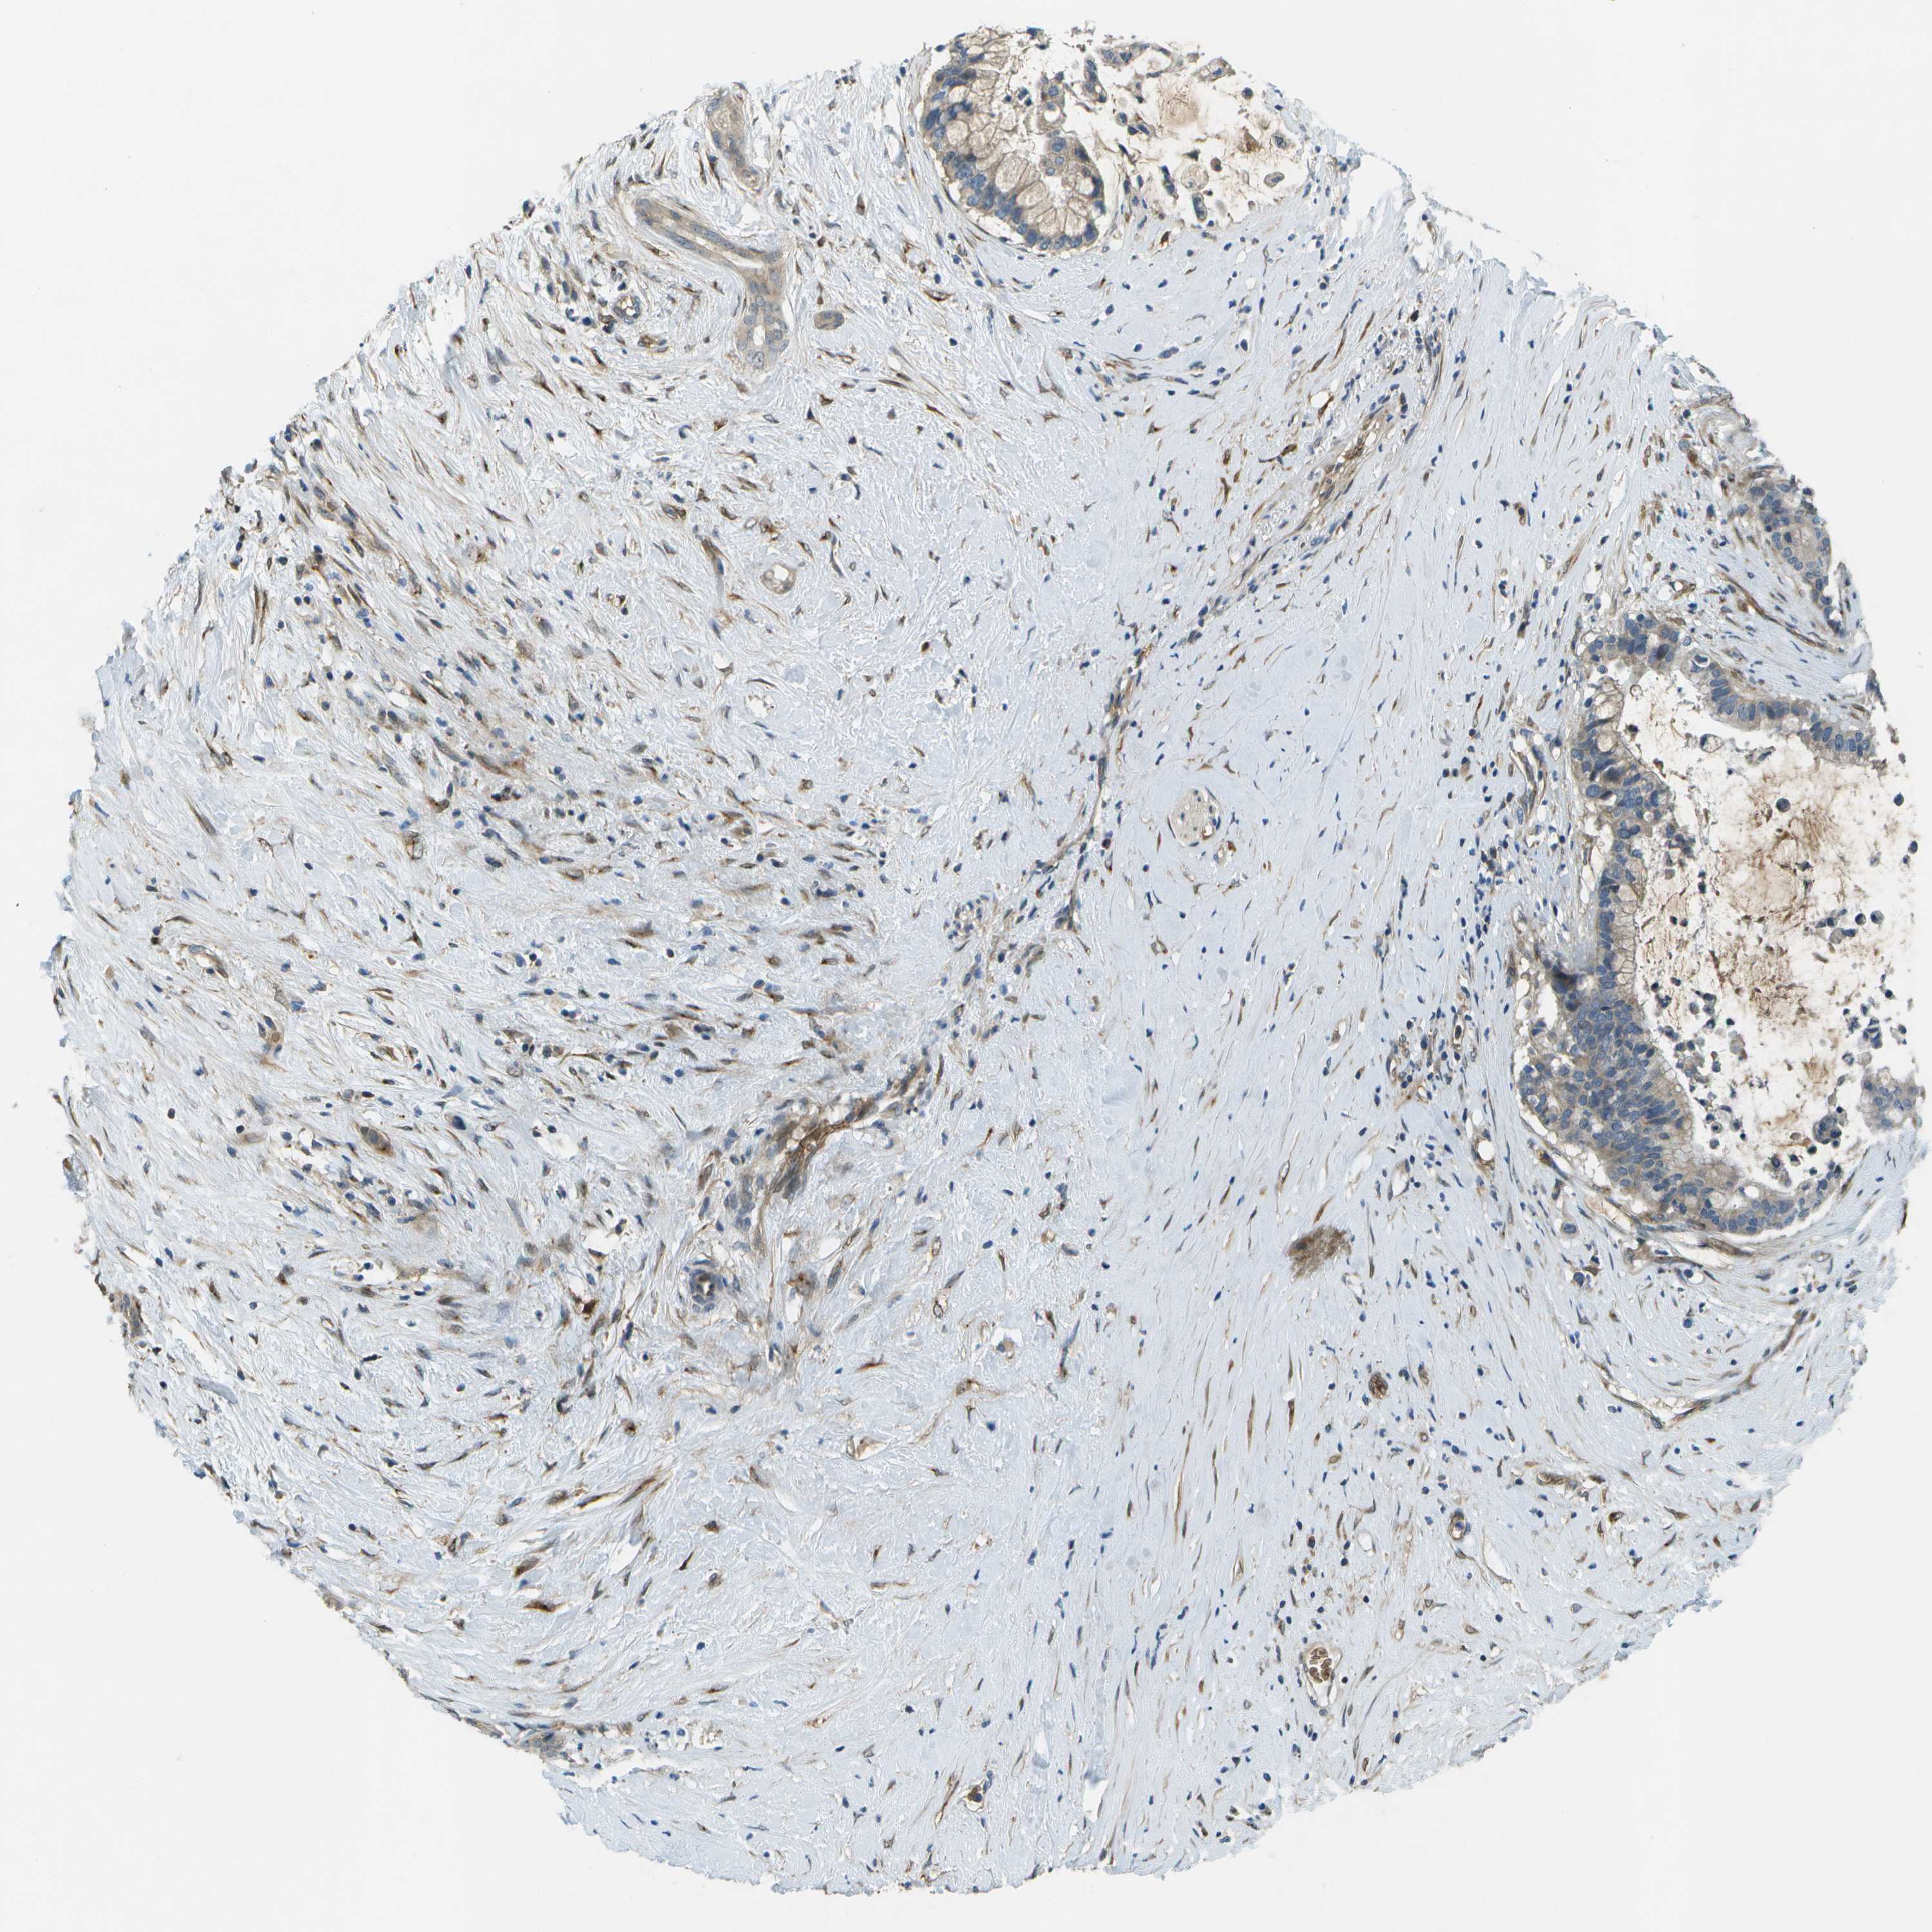

PANCREATIC CANCER - Protein expressioni

A mouse-over function shows sample information and annotation data. Click on an image to view it in a full screen mode. Samples can be filtered based on level of antibody staining by selecting one or several of the following categories: high, medium, low and not detected. The assay and annotation is described here.

Note that samples used for immunohistochemistry by the Human Protein Atlas do not correspond to samples in the TCGA dataset.

Antibody stainingi

Antibody staining in the annotated cell types in the current human tissue is reported as not detected, low, medium, or high, based on conventional immunohistochemistry profiling in selected tissues. This score is based on the combination of the staining intensity and fraction of stained cells.

Each image is clickable and will lead to virtual microscopy that enables deeper exploration of all samples and also displays staining intensity scores, fraction scores and subcellular localization as well as patient and tissue information for each sample.

Antibody HPA016865

Antibody HPA024801

Staining

High

Medium

Low

Not detected

Intensity

Strong

Moderate

Weak

Negative

Quantity

>75%

75%-25%

<25%

None

Location

Nuclear

Cytoplasmic/membranous

Cytoplasmic/membranous,nuclear

Adenocarcinoma, NOS